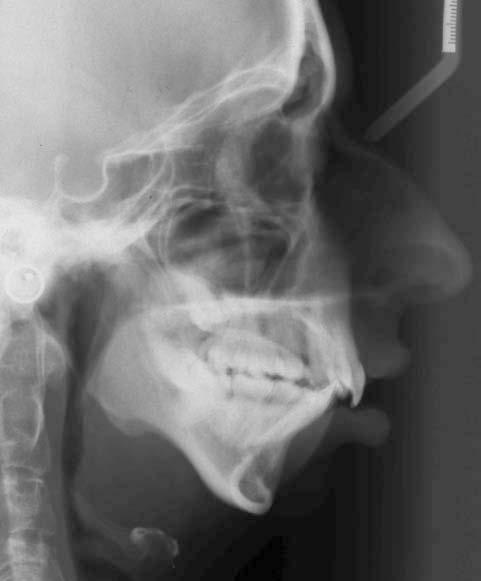

Figure 1.13 Lateral skull radiograph showing a class III malocclusion in an adult resulting from excessive growth hormone secondary to a pituitary tumour. Note the indistinct and enlarged borders of the pituitary fossa.

Overproduction of growth hormone from an anterior pituitary tumour causes gigantism in children and acromegaly in adults. In both circumstances, the patient presents with a worsening class III malocclusion characterized by mandibular excess (Fig. 1.13).